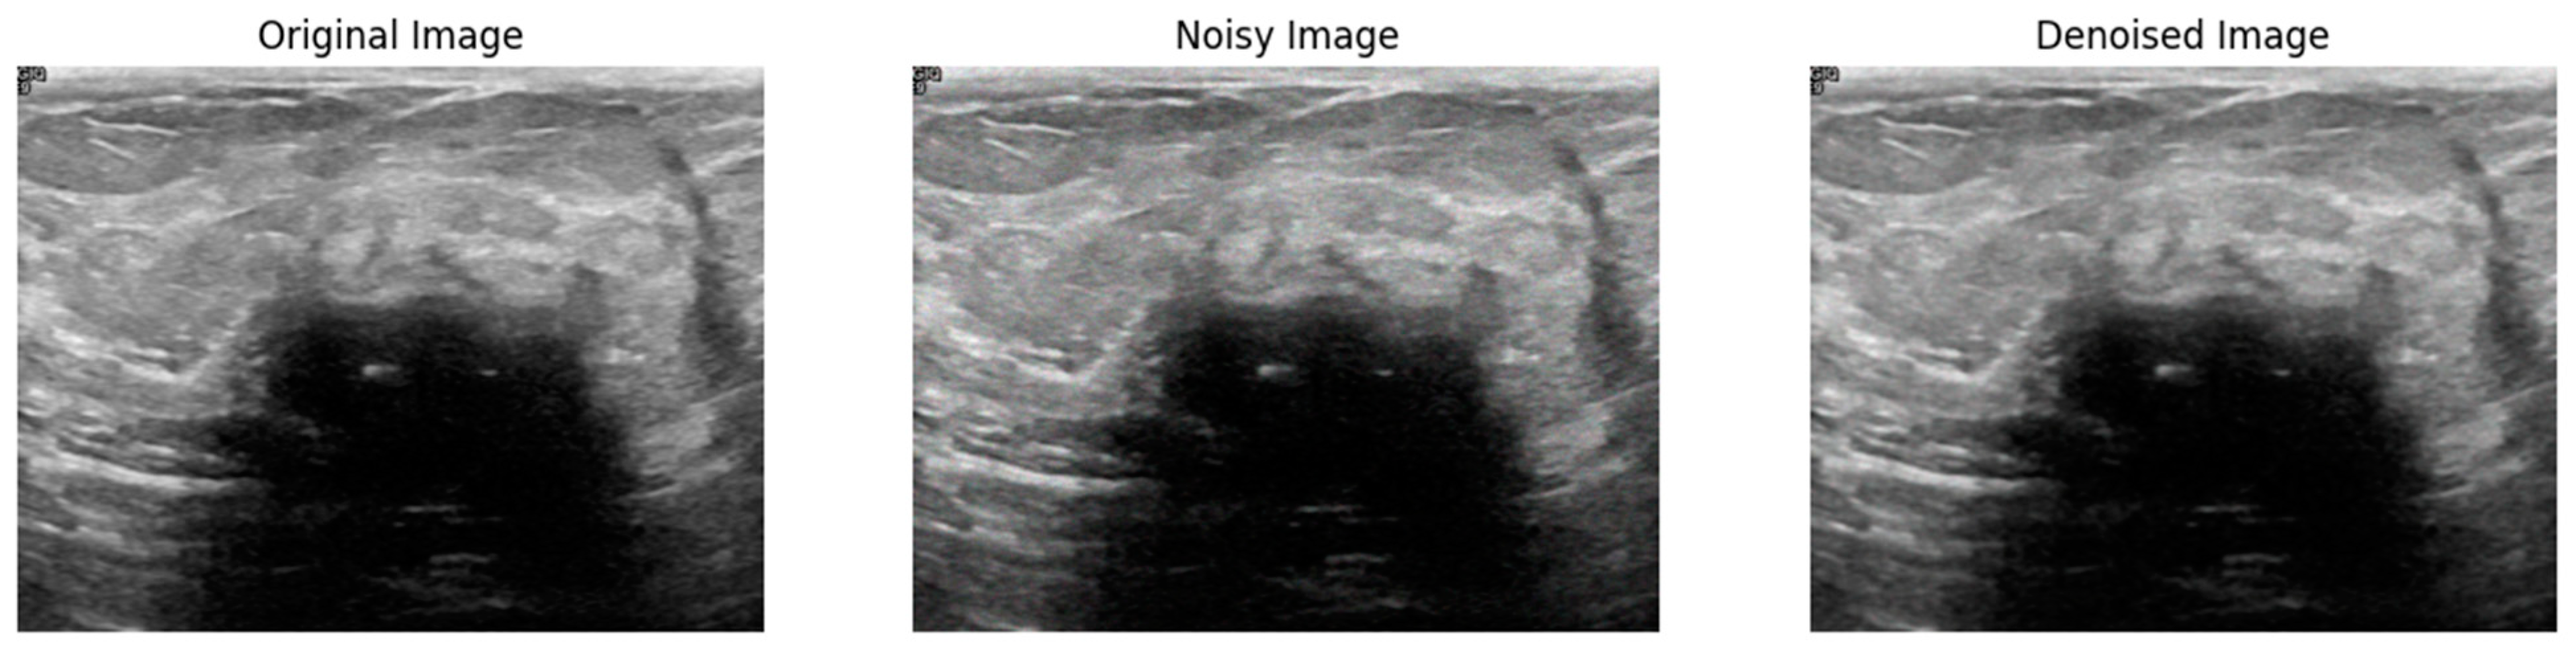

Figure 2 illustrates the visual effectiveness of the proposed denoising method. The figure displays three images for comparison: the original noise-free image, the image corrupted by Gaussian noise, and the image after being denoised using the proposed method. This visual comparison provides a qualitative assessment of the denoising performance, supplementing the quantitative results discussed earlier. The original image serves as a reference, showing the image without any noise interference. The noisy image, corrupted by Gaussian noise, exhibits significant visual distortions that obscure finer details and compromise the visibility of important structural information. In contrast, the denoised image produced by the proposed method shows a remarkable reduction in noise levels, with enhanced clarity and preservation of structural details. This comparison clearly demonstrates the ability of the proposed method to effectively remove noise while maintaining the quality and integrity of the original image.

Figure 2.

Visual comparison of the proposed method on Gaussian noise.

Figure 3 shows a visual comparison of the original image, the image corrupted by Poisson noise, and the denoised image produced using the proposed method. The original image serves as a baseline, displaying clear and noise-free content. The second image illustrates the significant noise introduced by Poisson distortion, which impacts image clarity and detail. In contrast, the final image demonstrates the effectiveness of the proposed denoising method, showing a substantial reduction in noise and an enhancement in image quality while preserving critical details. This comparison highlights the ability of the proposed method to effectively restore the image and mitigate the adverse effects of Poisson noise.

Figure 3.

Visual comparison of the proposed method on Poisson noise.